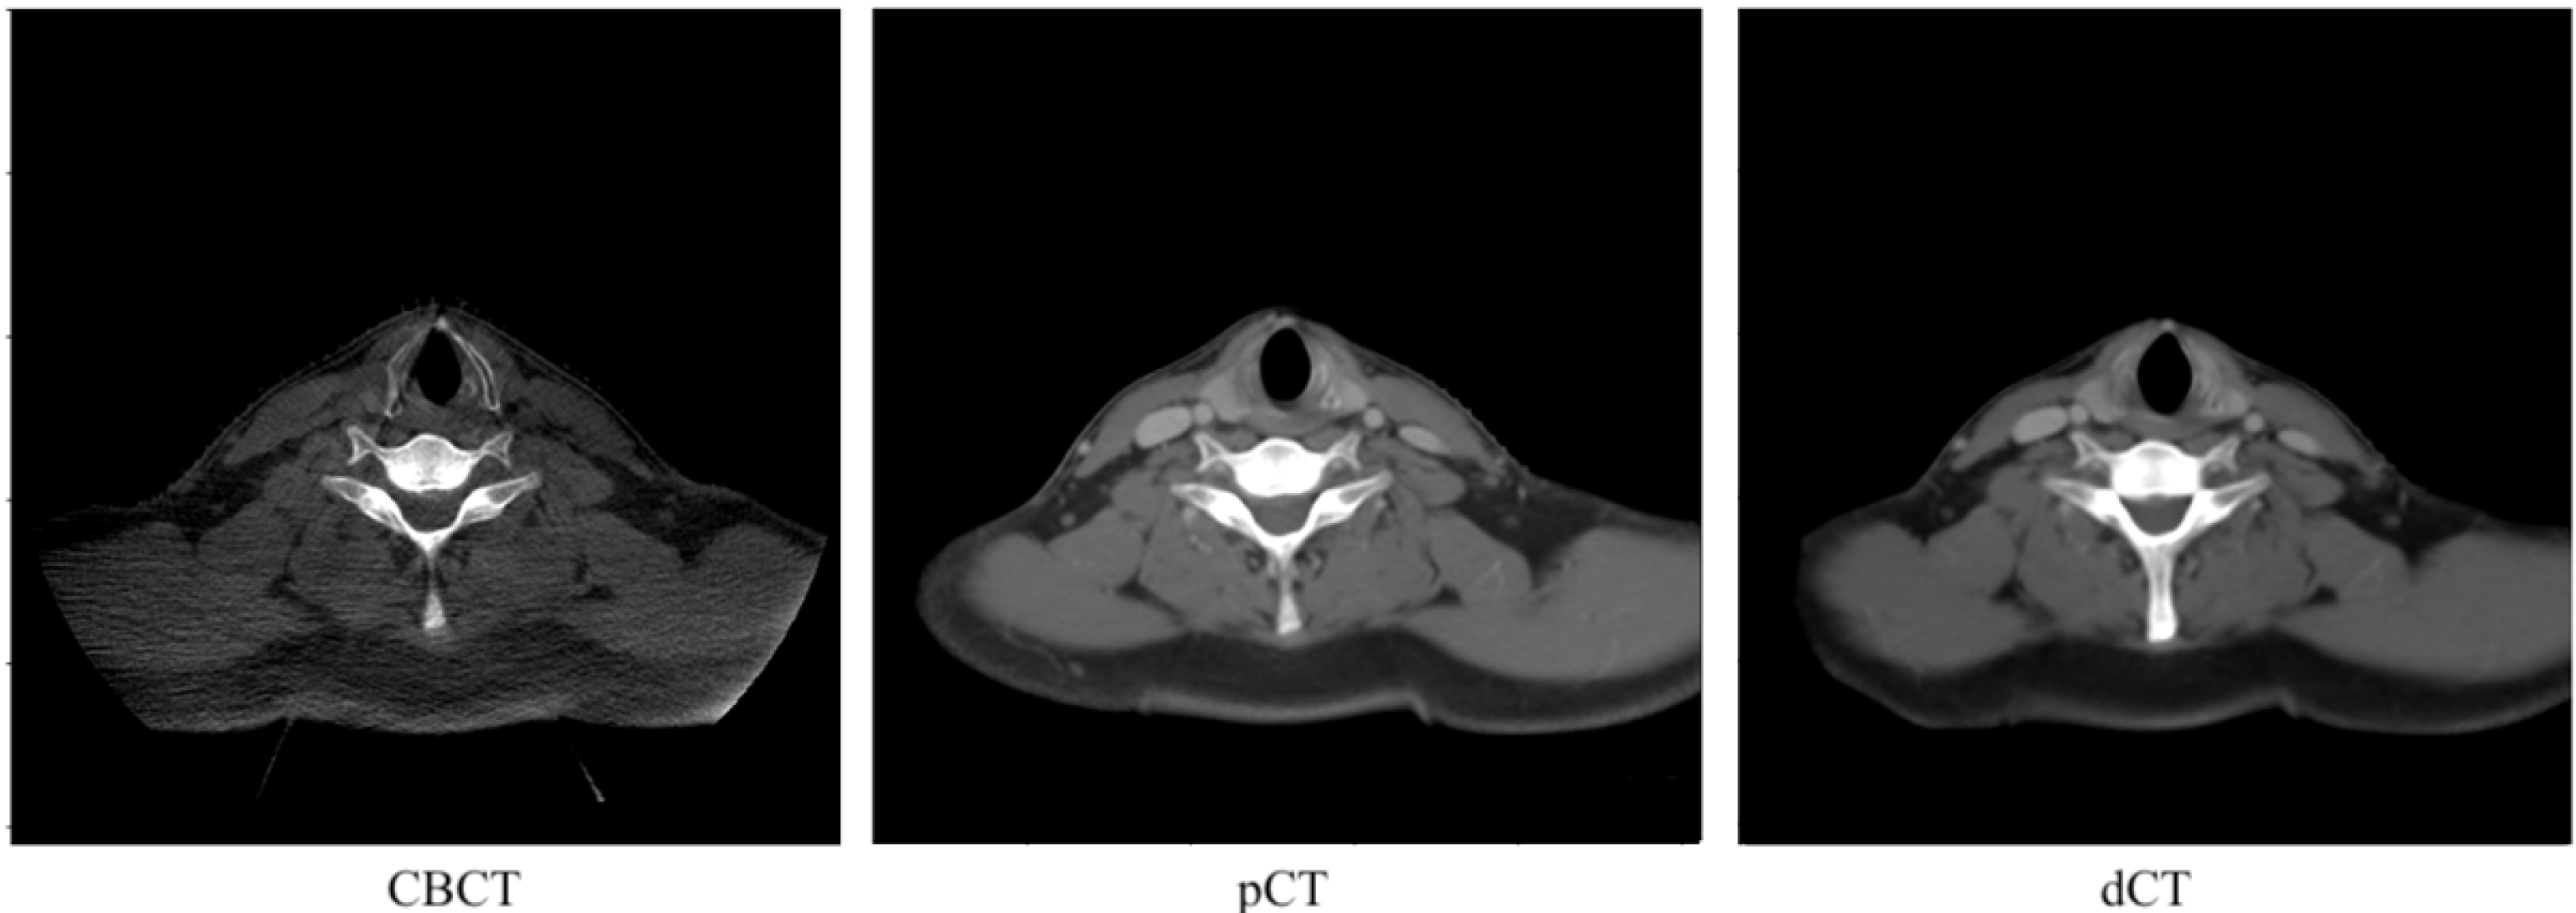

3. Results

3.1. Image Quality Evaluation with Quantitative Metrics

3.2. Image Quality Evaluation in Preserving Anatomy